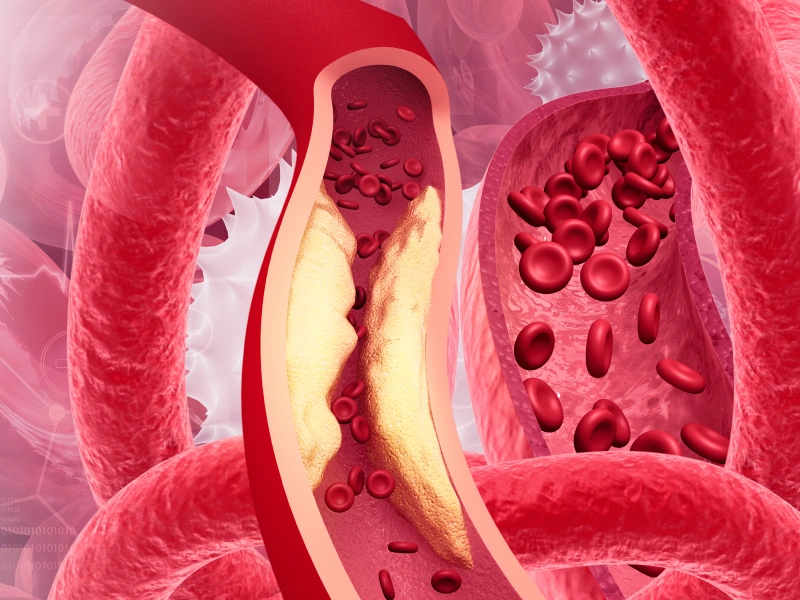

Aterosklerosis – pengerasan arteri

Penyakit jantung koronari

Penyakit arteri periferi

Pengurangan risiko kardiovaskular – kurang aterosklerosis, risiko serangan jantung dan strok menurun.

Rawatan Dislipidemia dengan Pembedahan Bariatrik Di Malaysia